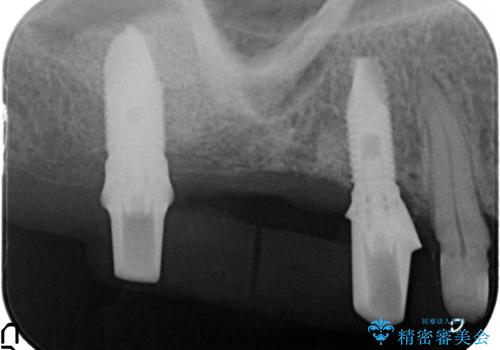

検査の結果、感染根管や欠損、歯周病により残すことのできない歯、等多々問題が認められます。

残すことのできる歯できない歯を選別し、欠損部にはインプラントによる咬合機能の回復、保存できる歯には歯周病治療・根管治療を行う治療計画としました。